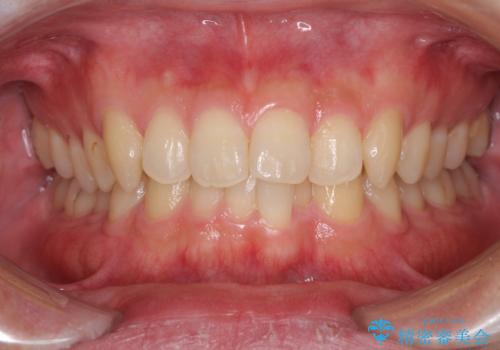

前歯の咬み合わせとデコボコを解消 インビザラインによる矯正治療

担当医 藤巻太一朗

インビザライン 前歯のがたつきを目立たず矯正

口が少し閉じにくい インビザラインによる非抜歯矯正